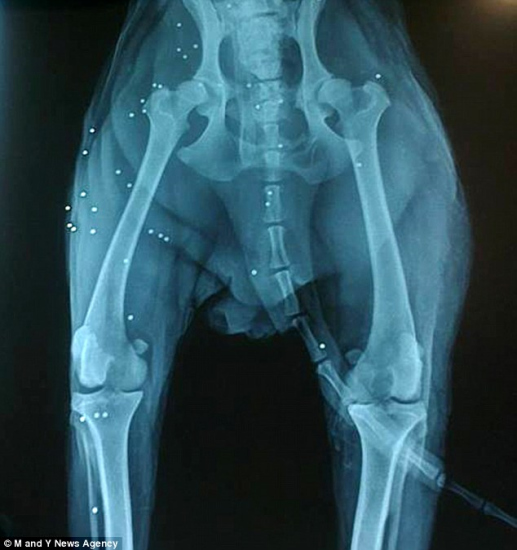

罗密欧因被弹丸枪击中38枪而躺在水沟里奄奄一息

中新网12月8日电 据英国《每日邮报》7日报道,近日,在希腊扎金索斯岛上,一只名叫“朱丽叶”的小狗为了解救受伤同伴“罗密欧”,守护在其身边三天三夜。罗密欧被弹丸枪击中38枪,躺在水沟里奄奄一息。然而朱丽叶在附近草地上守护期间,狂吠不止,希望引起路人的注意。

幸运的是,一名路人发现了罗密欧和朱丽叶,并将其带往当地的一家宠物医院进行救治。罗密欧在医院进行了10天的医治,目前身体状态已经改善。

名叫劳拉·桑提尼的兽医表示:“罗密欧当时非常虚弱,但幸运的是它现在已经好多了。罗密欧病情严重,能够活下来真是万幸。”